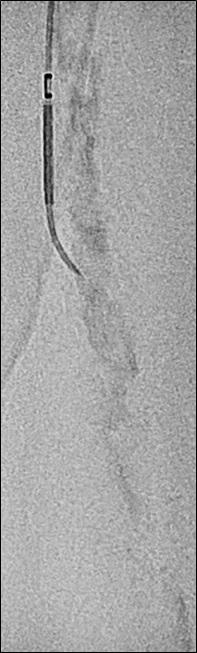

1. CTO of the left superficial femoral artery in a male patient suffering from severe claudication in the left calf

2. After subintimal passage, it was impossible to redirect the guidewire into the patent lumen distal to the CTO

3. Positioning of the BeBack catheter to re-enter the guidewire. Arrow indicates an orientation-marker

4. Marker appearing as a “C” indicates the direction of the needle, with the needle protruding maximally out of the BeBack catheter

5. An 0.018” guidewire passing into the patent distal lumen

6. Result after stenting